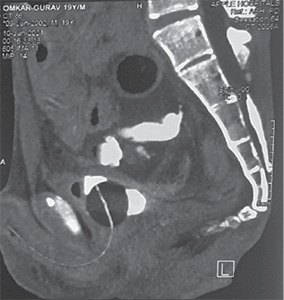

He was resuscitated with 1 500 ml of crystalloids through a left subclavian central line. Contrast-enhanced CT of the abdomen revealed perforation of the urinary bladder and extravasation of free urine into the pelvic cavity. It also revealed pneumointestinalis and grossly dilated bowel loops till mid transverse colon. There was a cut-off point at the level of the mid transverse colon (Figure 1).

Figure 1. Contrast enhanced computed tomography abdomen pelvis showing A – axial view showing dilated ascending colon, proximal transverse colon, intraperitoneal fluid collection B – extravasation of urine inside peritoneal cavity with pelvic collection